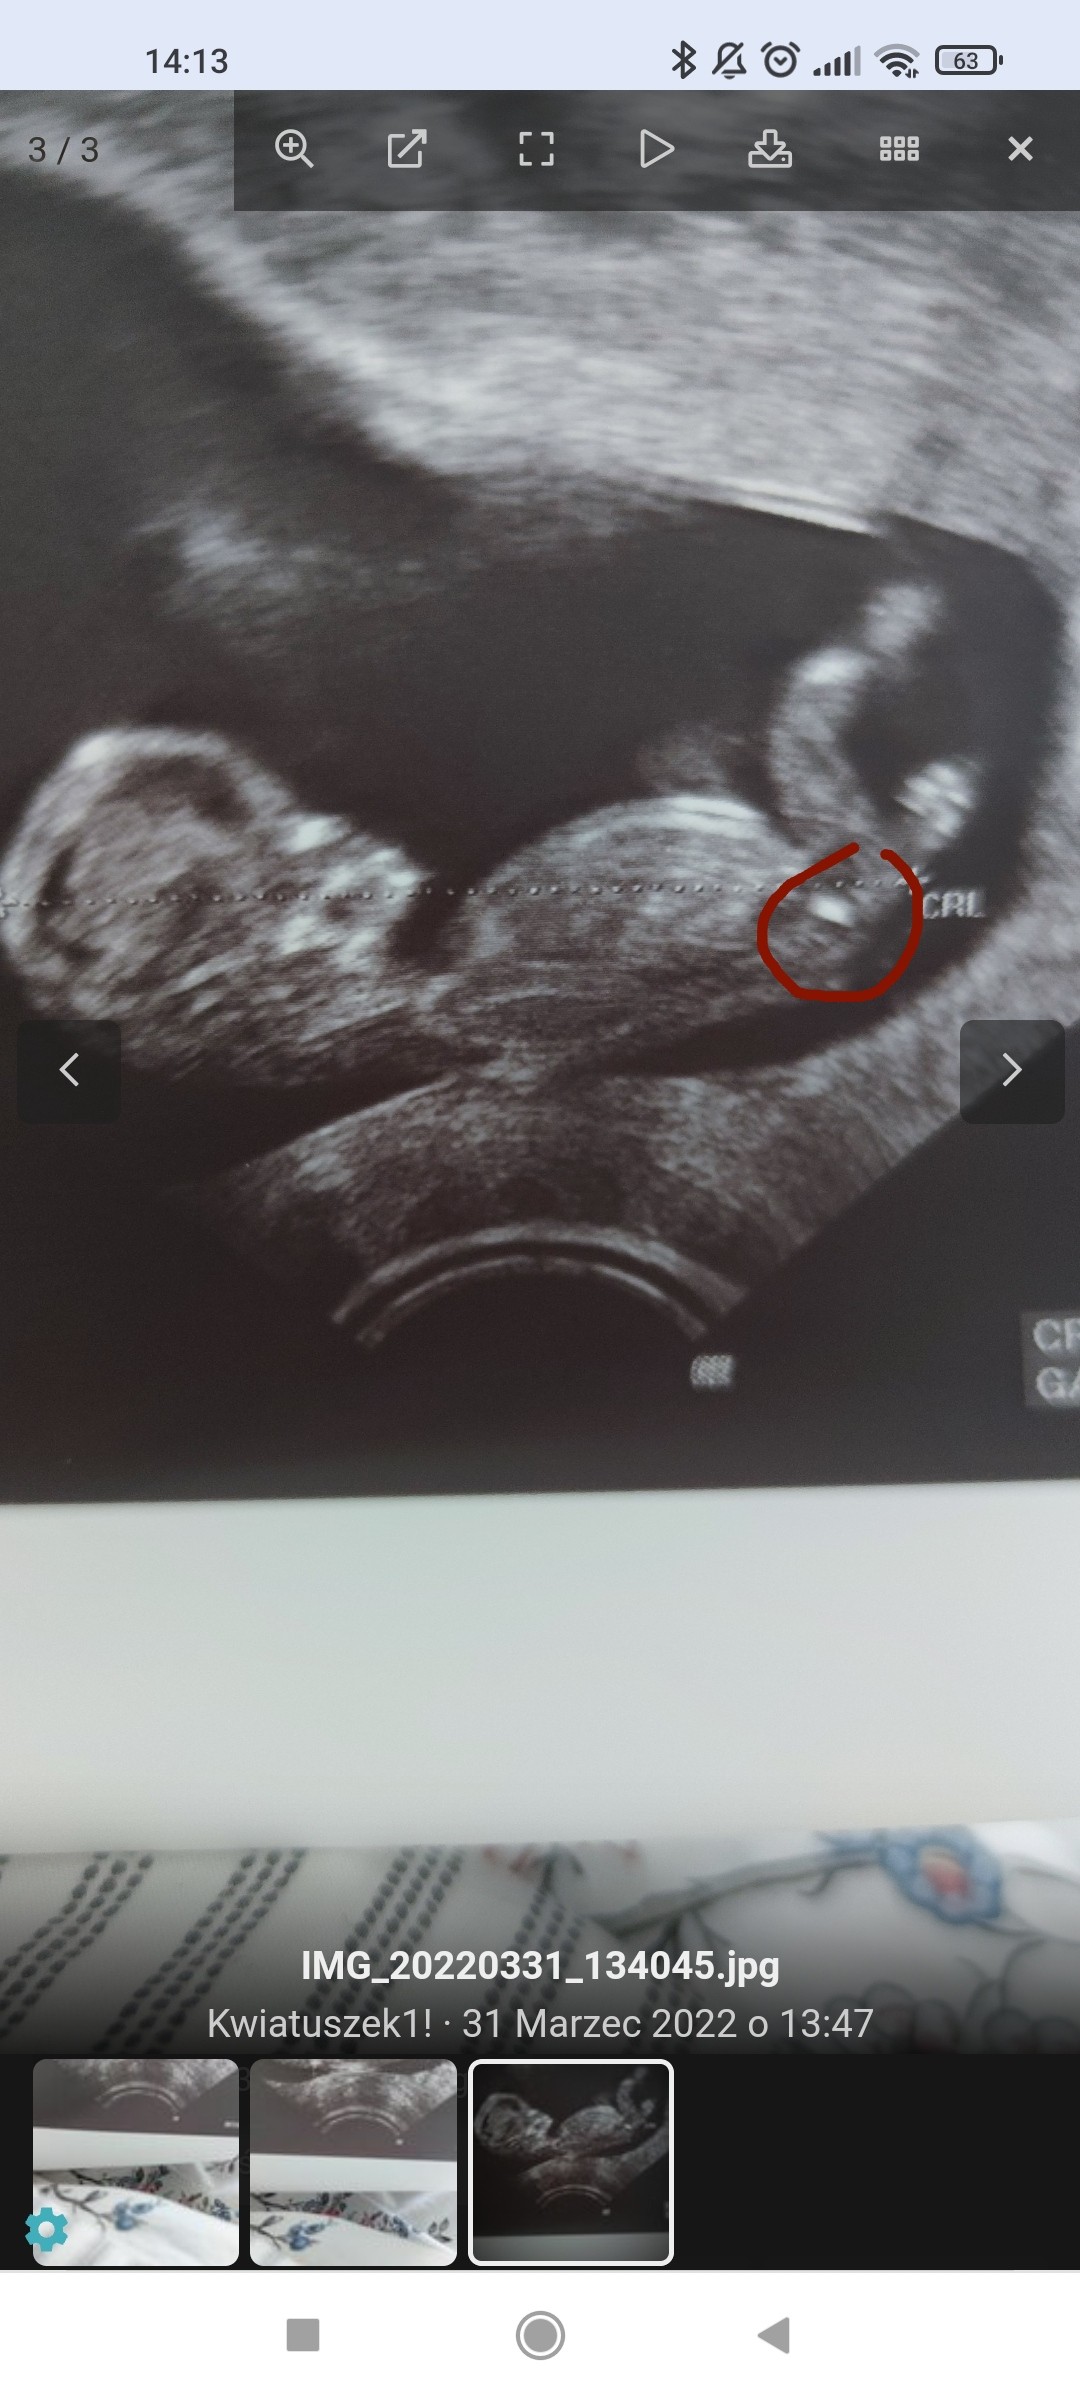

100% chlopak( usg)?Jak myslicie?

Jeśli ta biała jaśniejsza kreseczka to wyrostek, to bardziej wskazywałoby to na dziewczynkę.

Ale ja nie jestem lekarzem, więc nie ma pewności czy ta kreseczka to wyrostek 😂

To masz na mysli co zaznaczylam w koleczku? Kurka nawet nie zauwazylam tego wczesniej i faktycznie tutaj " to cos" jest skierowane ku dolowi🤔dalas mi do myslenia

... Bo ja to bardziej szukalam czegos sterczacego lub plaskiego wzdlug kregoslupa...ale tutaj ewidentnie na kazdym zdjeciu jest chyba zasloniete nozkami... Ale kurcze faktycznie...ta biala struktura ( kreseczka o ktorej mowisz) jest konkretnie wyodrebniona i zwrocona ku dolowi. Teraz mam do myslenia😃. Powiem Ci, ze jestes bardzo spostrzegawcza. Choc ponoc ja do takowych naleze😃a kurna w ogole na to nie spojrzalam...a teraz jak powiedzialas to tylko to widze😆

Tak - to miałam na myśli. Ale czy to jest ten wyrostek płciowy, to nie mam pojęcia.

Na zdjęciach w necie nieco inaczej wygląda - bardziej cienka na linia jest.